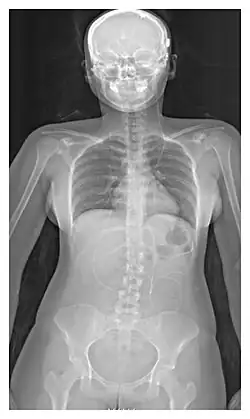

The location of the shunt is determined by the neurosurgeon based on the type and location of the blockage causing hydrocephalus. All brain ventricles are candidates for shunting. The catheter is most commonly placed in the abdomen but other locations include the heart and lungs.[11] Shunts can often be named after the route used by the neurosurgeon. The distal end of the catheter can be located in just about any tissue with enough epithelial cells to absorb the incoming CSF. Below are some common routing plans for cerebral shunts.

| Ventriculo-peritoneal shunt (VP shunt) | Peritoneal cavity |

| Ventriculo-atrial shunt (VA shunt) | Right atrium of the heart |

| Ventriculo-pleural shunt (VPL shunt) | Pleural cavity |

| Ventriculo-cisternal shunt (VC shunt) | Cisterna magna |

| Ventriculo-subgaleal shunt (SG shunt) | Subgaleal space |

| Lumbar-peritoneal shunt (LP shunt) | Peritoneal cavity |